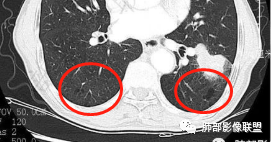

一般来讲,鳞癌收缩力弱,胸膜凹陷及牵拉少见,空洞坏死多见,而此例出现了“胸膜凹陷”,如下图:

这种特点在鳞癌比较多见  周围型鳞癌经常这个形态,外周有类似喇叭样收缩形态,考虑周围型鳞癌引起局部肺不张,所以有远侧内收而缺乏侧面收缩力。

——————摘自群里老师观点

回头看发现肿块近肺门侧边缘清楚,而远肺门侧边缘模糊,多考虑肿块阻塞支气管引起的阻塞性炎症,支持周围性鳞癌引起局部肺不张观点,两者形态相似,易与胸膜凹陷征混淆,小编认为,因肺不张为实变的肺组织,而胸膜凹陷为脏层胸膜受肿块牵拉凹陷形成的含液腔隙,故鳞癌形成的“胸膜凹陷”其密度较高,多为实性密度,而真正的胸膜凹陷征其内部密度较低,多为液体密度。